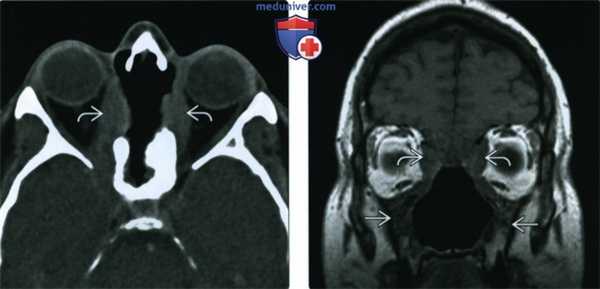

(Слева) На аксиальной КТ без КУ определяется деструкция верхних отделов носовой перегородки, перегородок между ячейками решетчатой кости, обеих глазничных пластинок (двухстстроннее поражение глазницы при гранулематозе).

(Справа) На корональной МРТ (Т1 ВИ) у этого же пациента определяется нарушение анатомии структур полости носа и утолщение стенок верхнечелюстных пазух. Жировые пластинки между патологически измененными мягкими тканями и медиальной прямой и верхней косой мышцами плохо различимы.

(Слева) При аксиальной КТ без КУ определяется деструкция верхней части носовой перегородки и глазничной пластинки с обеих сторон. В этом случае имеет место гранулематоз с распространением в обе орбиты.

(Справа) При корональной МРТ Т1ВИ у этого же пациента определяется нарушение нормальной анатомии носа и утолщение стенок верхнечелюстных пазух. Жировые пластинки между измененными мягкими тканями и внутренней прямой и верхней косой мышцами видны неотчетливо.